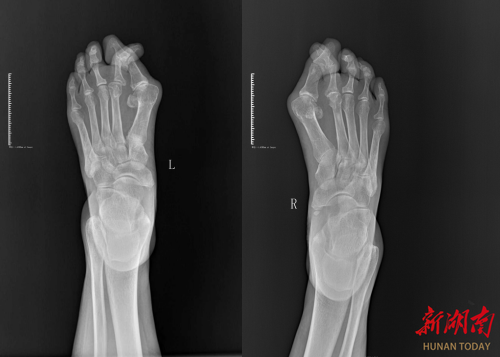

术后影像图。

如今,王女士的脚趾不再“挤作一团、乱成麻花”,而是乖乖“排好队伍”各司其职。益阳医专附属医院用“让脚趾归位”的通俗巧劲,把专业医术化作“解痛良方”,让患者重新迈出稳稳的幸福步伐。